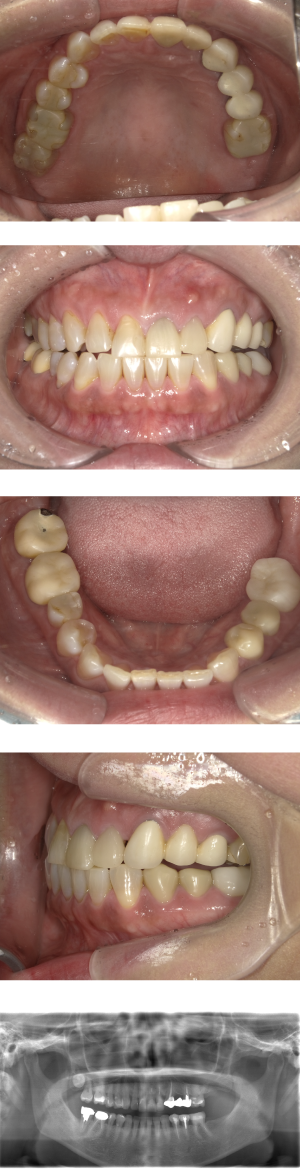

40代 女性 インプラント治療(右上64サイナス・GBR)

| 年代・性別 | 40代・女性 |

|---|---|

| 主訴 | 歯周病が進行し、抜歯適応となってしまったところにインプラント治療希望。 |

| 部位 | 右上⑥5④3② |

| 治療期間 | 約1年4ヶ月 |

| 費用 | ¥1,121,000(税込) |

| 副作用・リスク |

|